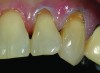

A 55-year-old woman presented with root decay along the left lateral incisor (tooth No. 10) and canine (tooth No. 11) (Figure 1). It was proposed that invisible Class V restorations be placed using an MMID procedure. There are several keys to attaining a successful invisible Class V restoration. Proper understanding of composite resin shade selection, preparation design, and sequence of composite resin layering are important to achieve an ideal blending of the composite resin to the existing tooth. Correct finishing and polishing technique is equally essential in obtaining a seamless esthetic restoration.3,11

Shade selection is always completed before initiating treatment; this is important to develop the proper shade-layering sequence. Composite shades were placed directly on the tooth and shades that matched the areas of the tooth being restored were chosen (Figure 2). To achieve an invisible Class V restoration, a more complex layering process is needed to blend the composite resin.